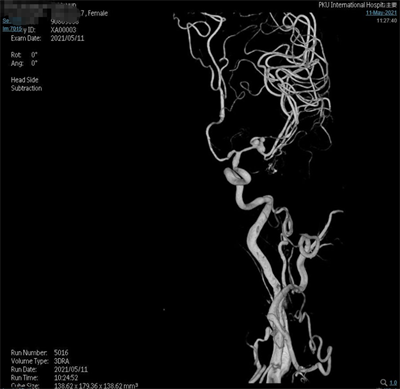

术前影像

脑动脉造影(外院,2021-5-10):双侧大脑中动脉分叉多发动脉瘤。

夹闭前造影